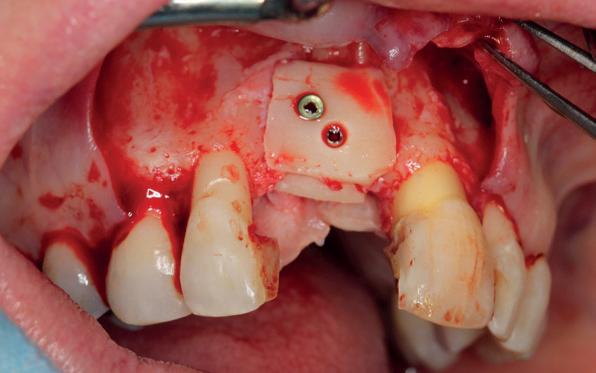

In het onderfront werd autoloog bot geoogst uit de kin regio ten behoeve van augmentatie (afbeelding

9. Botopbouw onderfront

9). In de bovenkaak werd bilateraal een sinuslift uitgevoerd. Aansluitend werden in beide kaakhelften implantaten geplaatst (afbeelding 10).